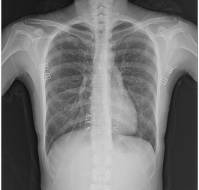

Children with atrial septal defect (ASD) and ventricular septal defect (VSD) are commonly examined for respiratory symptoms, even when the underlying condition is no..

A 15-year-old boy presented with shortness of breath and generalized malaise for over 3-4 days.The child had a history of Noonan syndrome. His medical history inclu..